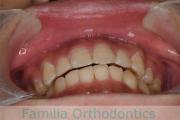

No.23V-132

- 主な症状:

- 開咬

- 年齢:

- 16歳

- 性別:

- 男性

- 抜歯部位

- 上:

- 88

- 下:

- 主な使用装置:

- FEA

- 治療にかかった費用:

- 87万円

開咬なので治療したいとのことで来院されました。受け口傾向のある開咬(前歯が咬み合わない)でしたので、下の親知らずを抜歯してマルチブラケット法にて治療を行いました。約1年半、20回程度の通院が必要でした。開咬は舌の癖の影響が強く、後戻りのリスクが高いケースといえます。